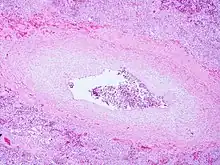

| Pulmonary veno-occlusive disease-Intimal fibrosis with marked narrowing of lumen of a large pulmonary vein | |

Pulmonary veno-occlusive disease may have a genetic basis. Published reports have indicated fatal occurrences that appeared to possess a familial pattern, more to the point, a germline mutation.[7] The pathophysiology of veno-occlusive disease culminates in occlusion of the pulmonary blood vessels. This could be due to edematous tissue (sclerotic fibrous tissue). Thickening is identified in lobular septal veins, also dilatation of lymphatics happens. Furthermore, alveolar capillaries become dilated (due to back-pressure).[8]